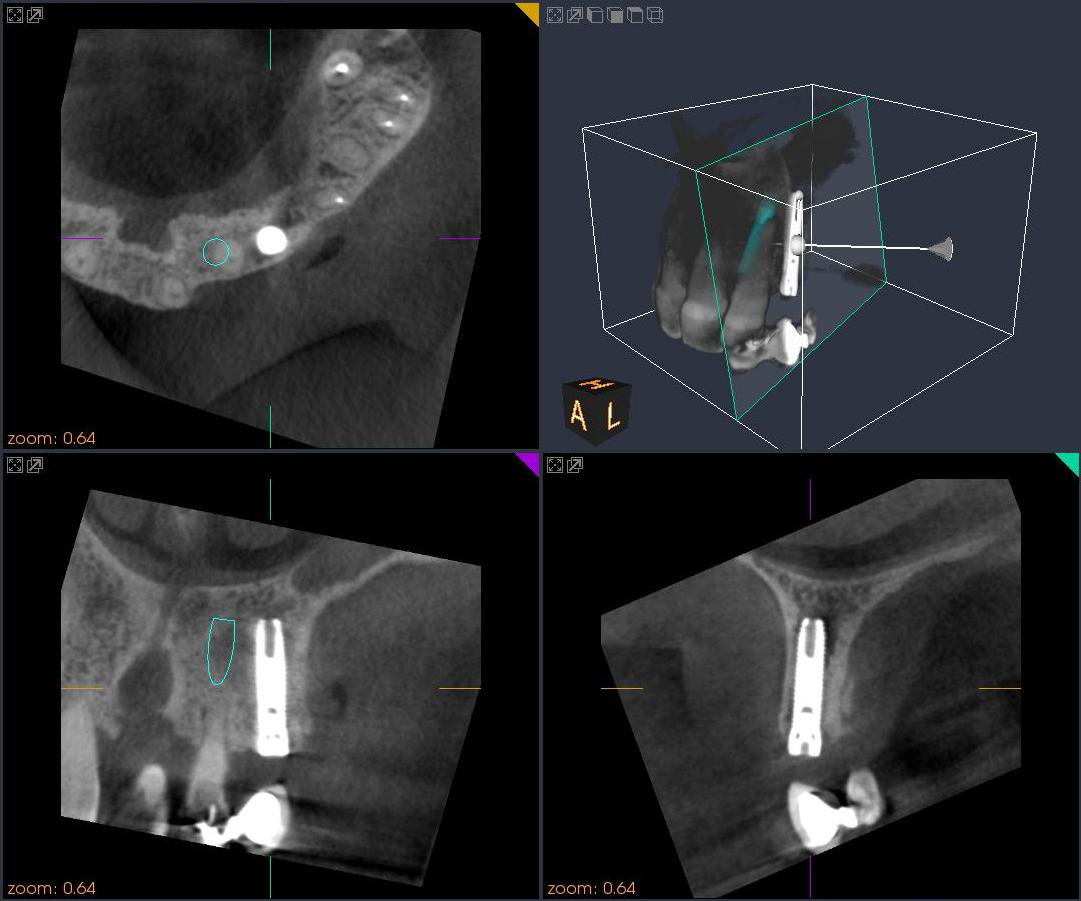

当医院では歯科用CTを導入しました。CTは立体的な画像で写し出されるため、インプラントのための診査や歯周病の

程度、親知らずの状態の把握を正確に行うことができ、より安全、確実に治療することができます。

CTによる3次元画像により、通常のレントゲン写真ではわからなかった部分が、精密・立体的に見ることができ、インプ

ラント治療の精度も飛躍的に向上します。

従来のX線写真は2次元的な平面での診断しかできませんが、歯科用CTスキャンでは3次元の立体画像でのレベル

に変わるので、より多くの情報が得られます。

<インプラント治療>

インプラントを埋める部位の骨の質や厚み・形態、神経・血管の位置が正確に分かり、確実な診断が可能となります。それにより、インプラント治療の安全性が飛躍的に向上します。

術中にもCT撮影ができることで、インプラントの位置や方向などの確認ができ、より安全・正確にインプラント手術をすることができます。

<歯周病治療>

歯の周囲の骨の破壊の程度が、立体的に把握でき、歯周病の進行度が正確に診断できます。それにより、最善の治療計画をたてることができ、治療の予知性が高くなります。